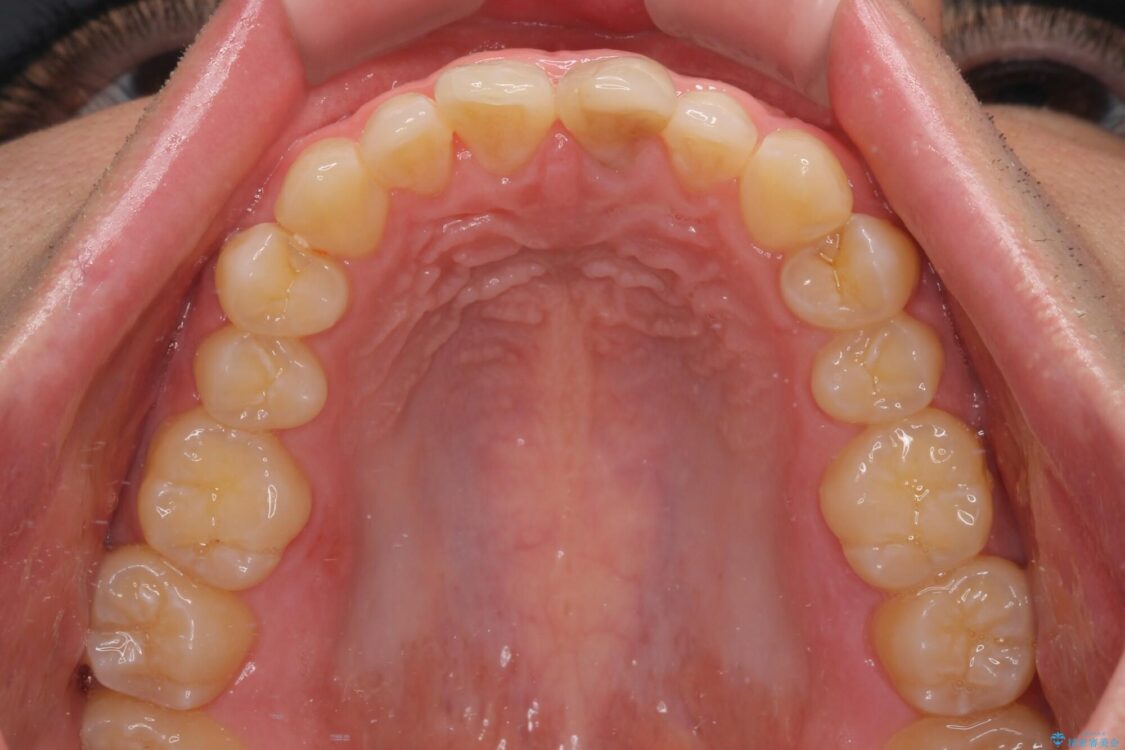

神経を取り除いたことで変色した前歯を気にして来院された患者様です。

根管治療はやり直さずに、ファイバーポストを使用した土台を植立してオールセラミッククラウンにて補綴することとしました。

治療前

• 変色した前歯をオールセラミッククラウンに 治療前画像